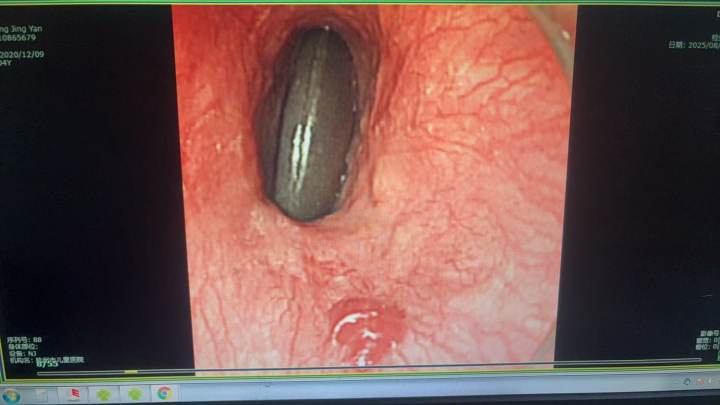

当晚,本该休息的王忠敏出现在医院时,家长连连道谢。在麻醉医生的密切配合下,王忠敏娴熟地操作胃镜,精准地找到了滞留在食管的围棋子,小心翼翼地将其取出。整个手术过程十分顺利,孩子安然无恙。